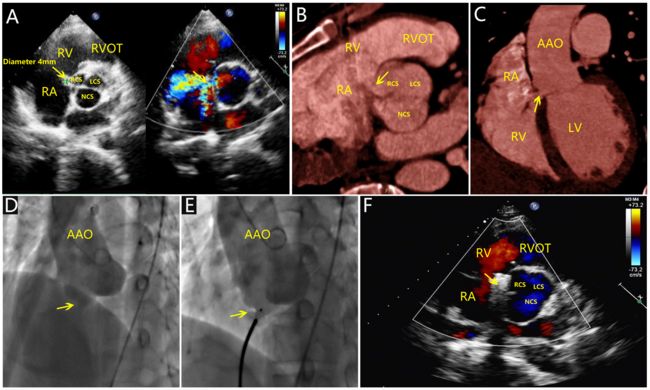

A 31-year-old man presented to our cardiac center with progressive dyspnea and fatigue. Physical examination revealed a continuous 3/6 systolic murmur at the lower left sternal border. Electrocardiography showed sinus tachycardia, while routine laboratory tests were normal. Transthoracic echocardiography (TTE) identified a 4-mm echo-free structure extending from the right coronary sinus into the right atrium. Color Doppler demonstrated a high velocity left-to-right shunt with peak velocity of 6.2 m/s and pressure gradient of 155 mm Hg, suggestive of aorto-right atrial fistula (Figure A). Contrast-enhanced computed tomography (CT) confirmed a ruptured right sinus of Valsalva aneurysm, with the defect located greater than 2 mm from the right coronary artery and aortic valve annulus (Figure B and C), indicating suitability for transcatheter closure.

The patient underwent successful percutaneous closure using a waist-shaped Cera VSD Occluder (Lifetech Scientific) (Figure D and E, Videos 1 and 2). Immediate post-procedural TTE showed complete elimination of the shunt with no residual flow or complications (Figure F). He was discharged 3 days post-procedure and resumed full-time work within 3 months.